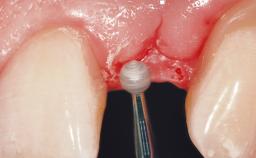

Immediate Flapless Placement of an Implant in a Maxillary Right Lateral Incisor Site

This 43-year-old male patient, a non-smoker, came to our practice because of a fracture of tooth 12 caused by a bicycle accident. Due to the combined para- and infrabony crown and root fracture, tooth extraction, and subsequent implant placement were suggested to the patient as the therapy of choice. The patient had high esthetic expectations with regard to the treatment outcome and asked for an immediate fixed provisional restoration. His individual esthetic risk profile summed up to a medium esthetic risk.

Placement Protocol Immediate implant placement

Socket Morphology Single-root socket

Socket Integrity Sufficient, with intact bone walls

Bone Volume Sufficient, with intact walls